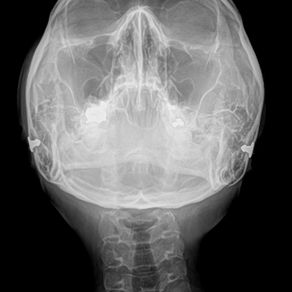

ブレア式:画像分析